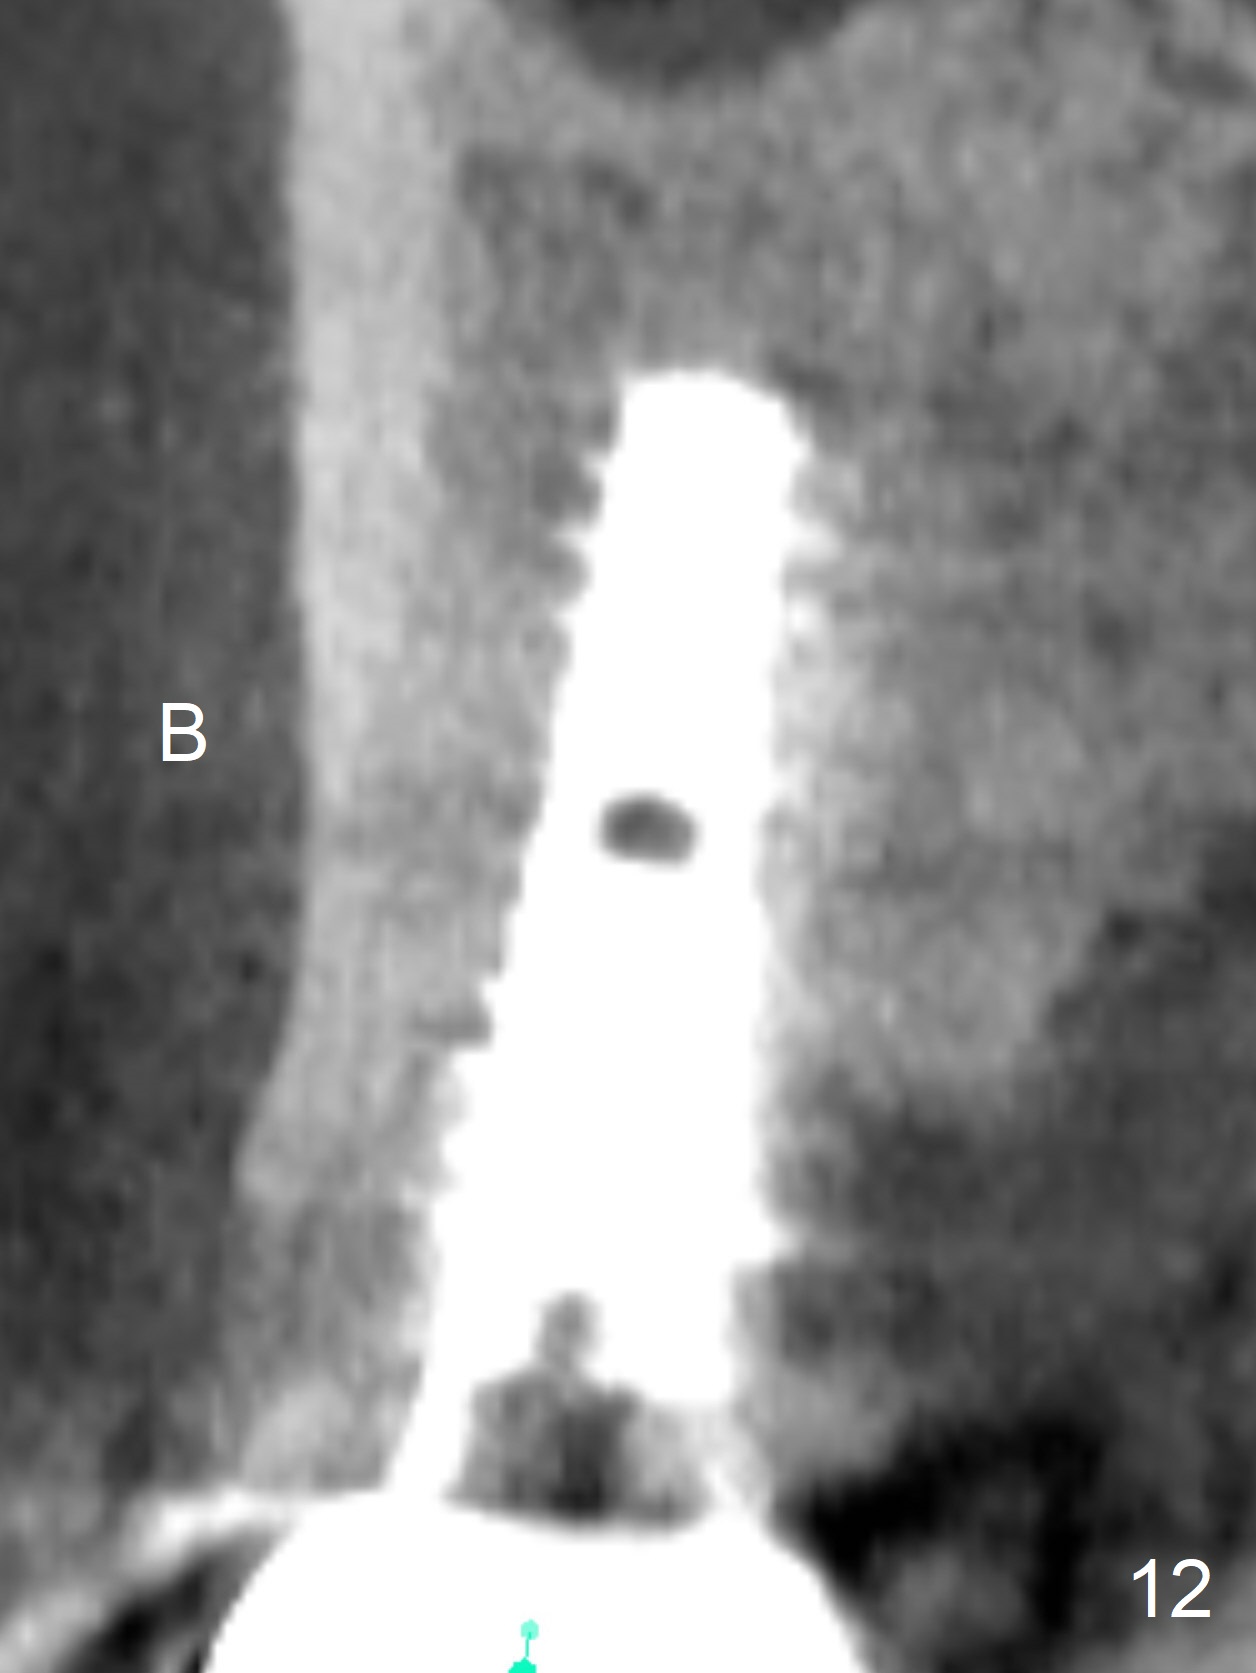

The distal papilla reforms buccally (Fig.8 *) and palatally (Fig.9) 4 months postop.  It appears that the 4 mm cuff of the pair abutment (Fig.10 >) is apical to the mesial crest (*).  The distal coronal implant threads seem to be covered by bone graft (Fig.11 <).  Therefore pair abutments with 5 mm or more cuff are required in cases of the uneven bone.   Implants have to be placed deep.  CT taken 3 months post cementation (10 months postop) shows that the implant is placed in the middle of the alveolus without apparent thread exposure.  CT taken 1 year and 8 months post cementation (Fig.13) shows that the implant is placed in the middle of the alveolus without apparent thread exposure, as compared to those at #2 and 3, which are placed buccal (B).